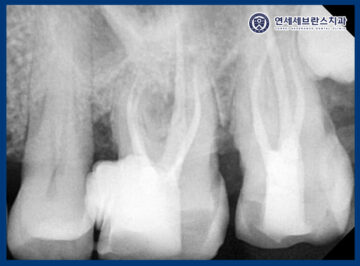

24.09.19

이후 환자분께서 시간을 많이 빼기 힘든 상황으로

일단 통증 발생의 가능성이 있는

왼쪽 위 큰 어금니 신경치료 및 잇몸치료

먼저 진행하기로 하였습니다.

보철 치료의 경우에는

추후 임플란트 식립 시기와 맞추어

전체적인 교합과 기능을 고려해 함께 진행하기로

치료 계획을 수립하였는데요.

이처럼 신경치료를 통해

감염된 신경 조직을 제거하고

치아를 보존할 수 있는 기반을 마련하였습니다.

또한 잇몸치료를 통해

치아 주변에 쌓여 있던 치석과 염증을 제거하고,

잇몸 조직을 건강한 상태로

회복시키는 과정을 함께 진행하였습니다.